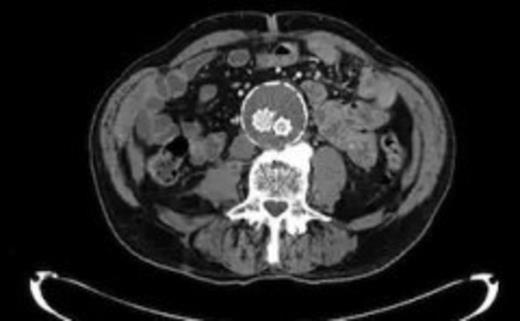

An 82 year old gentleman with known peripheral vascular disease and previous open popliteal aneurysm repair underwent endovascular repair of a 58mm infrarenal abdominal aortic aneurysm (Fig. 1) using a Cook Zenith bifurcated prosthesis The Zenith Flex® AAA Endovascular Graft (Cook Medical Inc., Bloomington, USA). The operation, which was performed under general anaesthetic and bilateral groin cut downs with intravenous prophylactic antibiotic cover on induction (Co-amoxiclav 1.2g) was uneventful. The main body was deployed via the right side. Completion angiograms showed satisfactory exclusion of the aneurysm sac with good graft position and no endoleaks. Post operatively the patient had a brief period of low grade pyrexia and lower abdominal pain that settled spontaneously. This was thought to be due to post implant graft reaction. Pre-discharge imaging with plain abdominal X-rays was deemed satisfactory.

Four weeks following discharge the patient was re-admitted with feeling increasingly unwell, recurrent pyrexia, loss of appetite and mild shortness of breath on exertion. Physical examination was unremarkable except for a temperature of 38.3 centigrade. Blood tests on admission showed Hb 11.4 g/dl (11.5-16.0 g/dl), white cell count 13.1×109/L (4-9.2 x 109/L) and CRP 68mg/L (<3 mg/L). Contrast enhanced CT scan (Fig. 2,3) showed a 50 mm maximum retroperitoneal collection situated between the right kidney and the right iliac vessels. It contained a few loculi of gas. A diagnosis of postoperative right psoas abscess was made. The patient was started on intravenous broad spectrum antibiotics – Tazocin (Piperacillin+ Tazobactam) and Metronidazole. CT guided drainage was carried out using a 10 French gauge pigtail catheter locked pigtail (Meditech Flexima regular all-purpose drainage catheter sets with locking pigtail (Boston Scientific)) (Fig. 4). The isolation of E. coli from the collection with negative Hemocultures suggested a bowel source for the infection but no actual breach was demonstrable. The bowel surgeons ruled out colonic pathology.

A 50 mm maximum retroperitoneal collection situated between the right kidney and the right iliac vessels